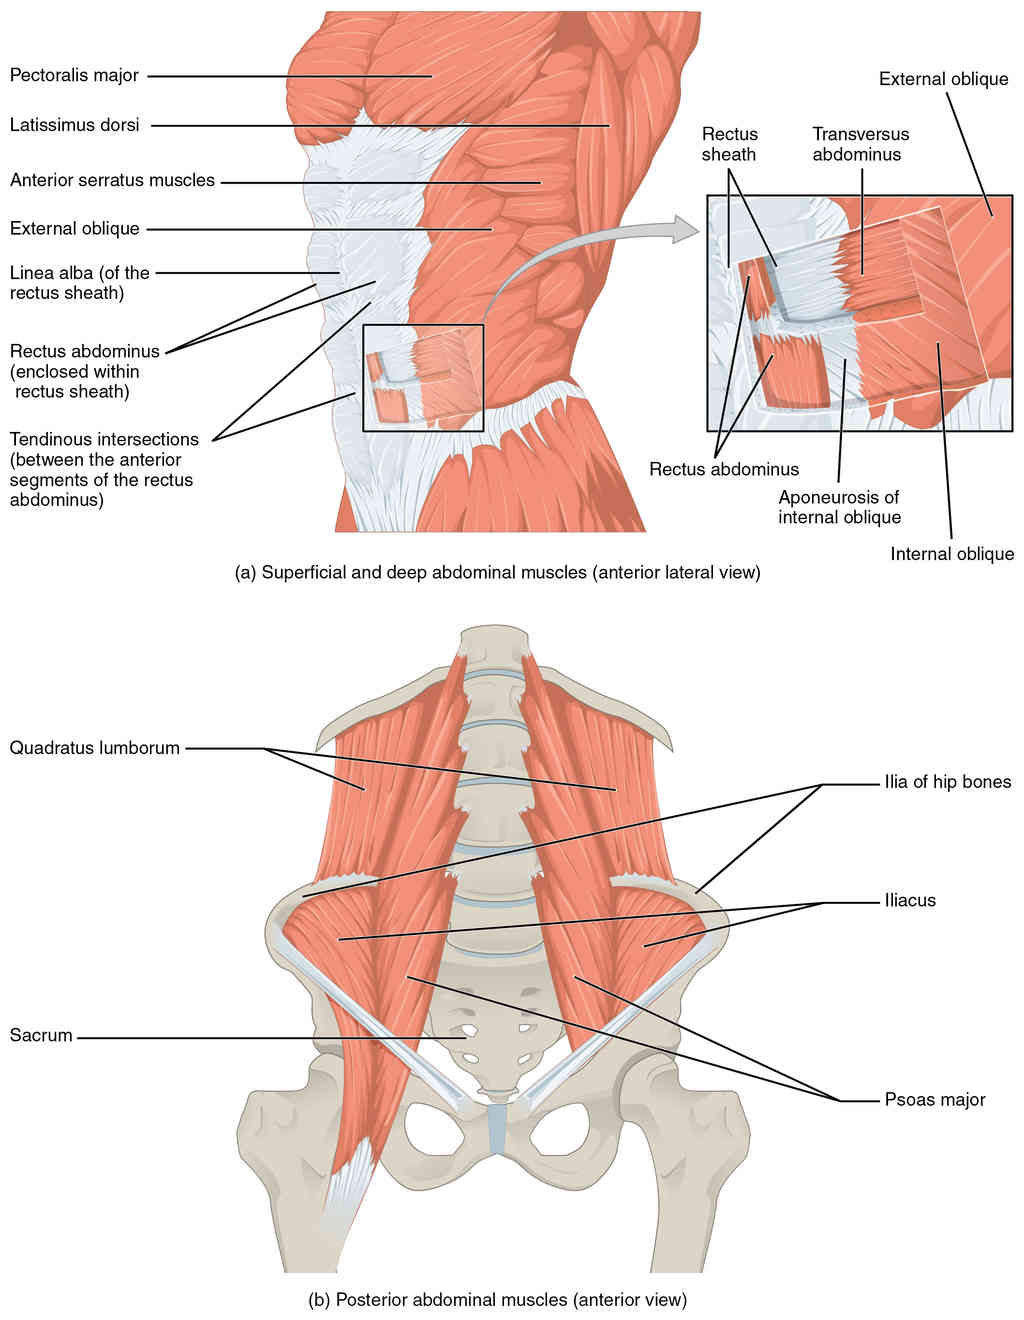

This page is under construction. For now, it is just a resource of the images found in the OpenStax Anatomy and Physiology Handbook. It wil slowly change into a revision tool. Each slide has a number. Use this to refer to the slide. When completed, it will have an unlabelled section, with labelled slides in parallel. On the unlabelled slides, write your answer and use the labelled slide to assess yourself. Keep track by also noting the number on each slide. Improvement at each attempt is important, more so than full marks on a first attempt.